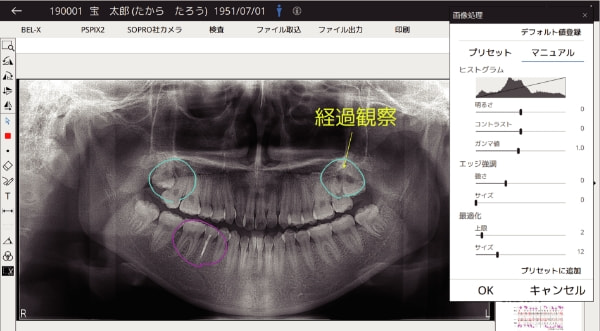

様々な機器やシステムからの患者情報を一元管理

一元管理ソフト「 MyGate(マイゲート )」

様々な機器やシステムからの患者情報を一元管理する患者情報統合システムです。

撮影のオーダーから画像取り込み、患者説明から印刷まで、スムーズに行うことができます。

各種フィルター、描画、注釈機能

画像処理や距離計測、テキスト・矩形の配置に加え、フリーハンドでの描画も可能です。

テキストは定型文としてプリセットもできます。

画像閲覧(パノラマ、デンタル、口腔内カメラ他)、レイアウト表示

パノラマ、デンタル、口腔内カメラなどの画像をあらかじめ選択したレイアウトで表示することができます。

レポート作成機能

患者さんへの説明資料や、保険診療の提供文書の作成ができます。

患者情報や撮影情報、医院情報またメッセージの配置も可能です。

メッセージはあらかじめ登録したプリセットから入力することもできます。